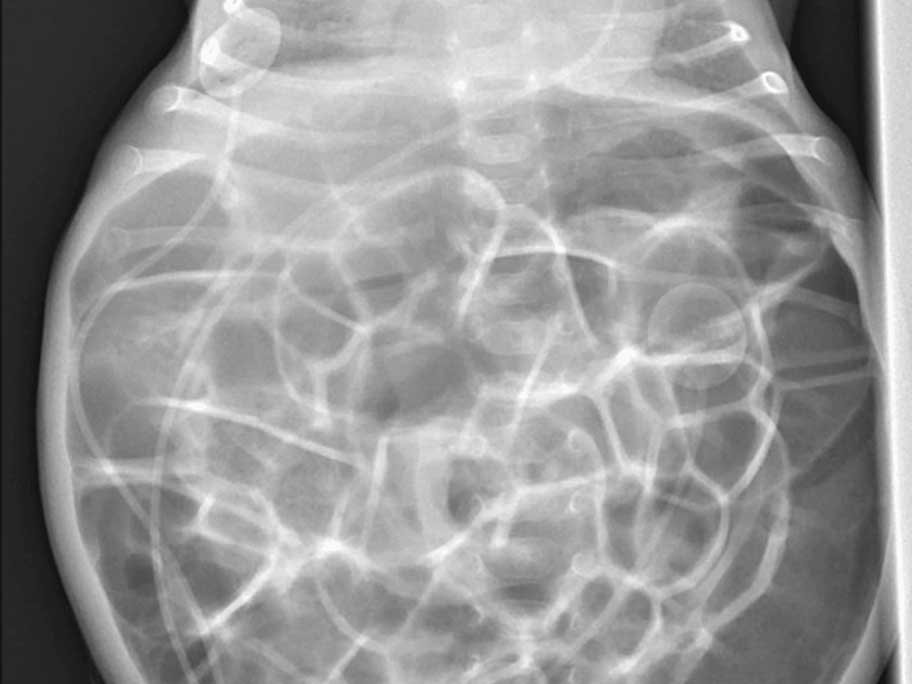

A Japanese woman escaped serious complications, including myonecrosis, following a simple elbow dislocation that morphed into acute compartment syndrome, doctors report. The case also highlights…